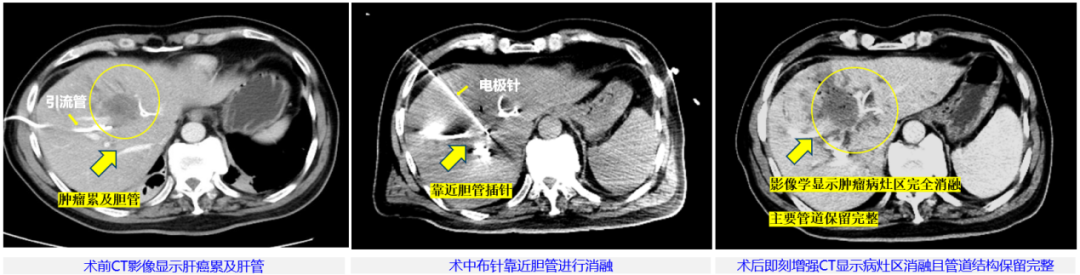

本次治療病例為57歲男性,臨床診斷肝內膽管細胞癌局部轉移,侵犯肝門伴梗阻性黃疸,主病灶45mm×36mm,已行雙側PTBD(經皮經肝膽管穿刺引流術)減黃處理。由于病灶位于肝門部,緊鄰左側門靜脈及膽囊,這里密布肝動脈、門靜脈和膽管等重要脈管結構,無法進行手術切除根治,也不適合各種冷/熱消融治療。董家鴻牽頭肝膽胰中心多學科討論后決定,為患者進行具有脈管保護優勢的“微納刀”消融治療。

整個手術過程中,患者行局部麻醉,在B超聯合CT引導下使用“微納刀”通過單針對病灶區進行消融,消融過程歷時15分鐘。術中未使用任何肌松劑,也沒有采用氣管麻醉,患者始終處于清醒狀態,可與醫生交流。脈沖施加過程中未見肌肉有明顯收縮反應,患者也無明顯的疼痛的感覺,術后即刻增強CT復查發現,腫瘤病灶區在影像學上已顯示全部消融,鄰近膽管、血管未見損傷。隨后患者安全返回病房,術中術后生命體征平穩、未發現不良反應。